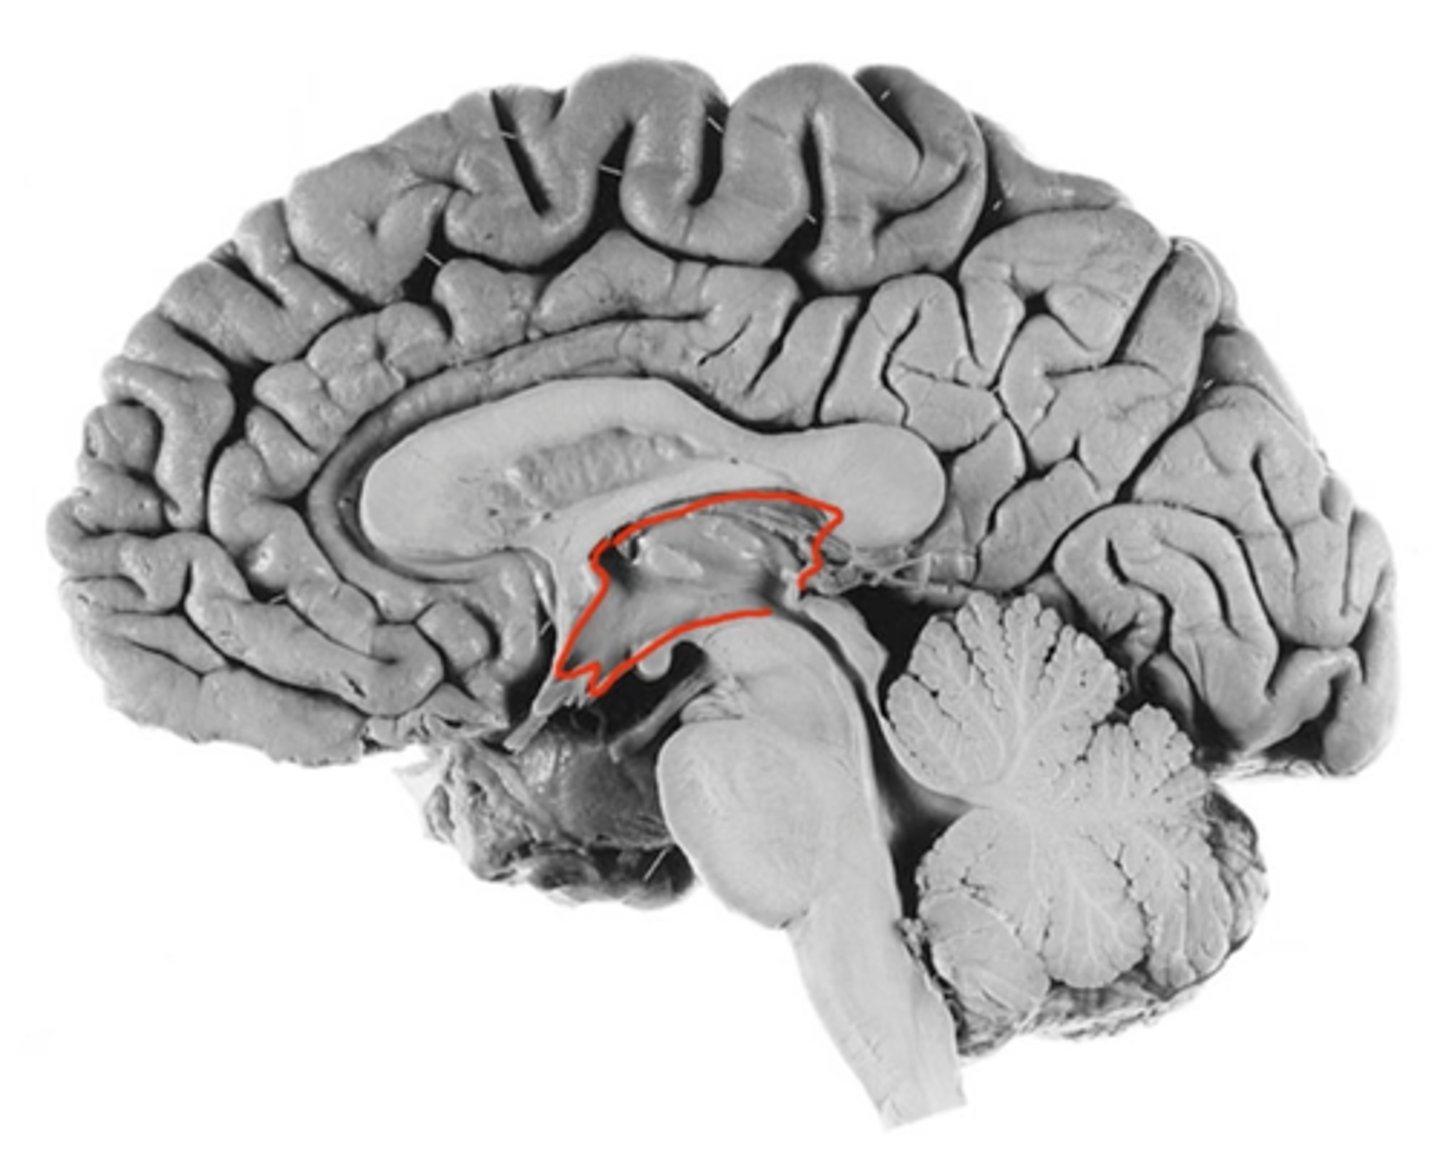

thalamus

hypothalamus